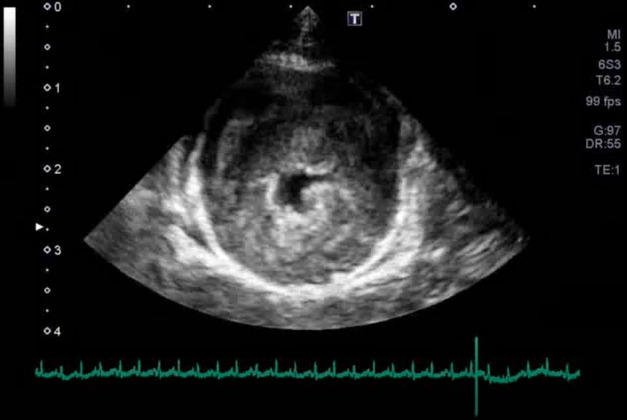

図3C 心原性肺水腫の猫における肺超音波画像

雑種猫、8歳5カ月齢、去勢雄、体重4.68kg。心疾患の管理中であったが、3日ほど投薬できておらず、かかりつけ医より紹介来院した。肺水腫によりB-lineの増加(white lung)が認められた。

特集 悩ましい猫の肺炎 vs. 肺水腫 vs. 肺腫瘍(塗木貴臣先生)図3Ⅽ